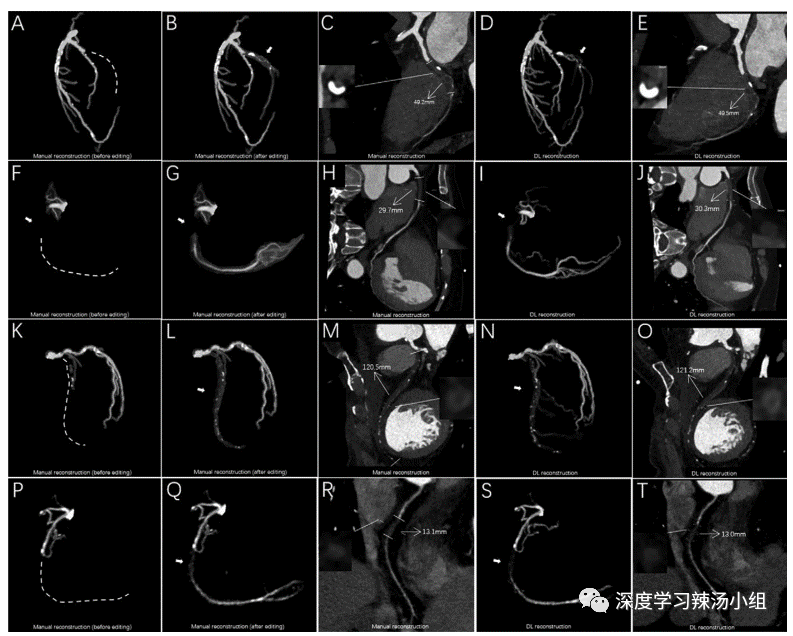

实验结果表明,利用深度学习模型95%的病变(240例病变中的228例)成功地实现了CTO的自动分割和重建,且无需手动编辑(图3)。在12例需要手动调整的病变中,11例病变在放射科医生手动生长血管后可以进行进一步的量化分析,而1例病变因为图像质量原因无法分割(图3S)。

图3:不同患者的重建对比